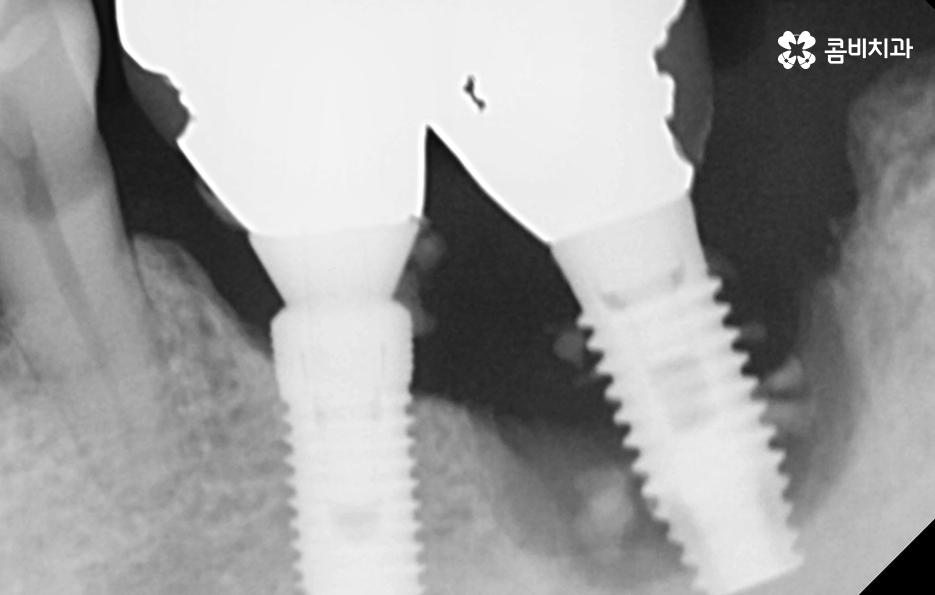

위 환자분의 케이스는 치주염이 심해져서 치아를 잃게 되기도 했지만 윗니의 경우 브릿지로 치아 기능을 유지하다가 결국 임플란트를 하게 된 사례로 볼 수 있어요

과거에는 임플란트 치료 자체가 없어서 브릿지나 틀니와 같은 치료를 할 수 밖에 없었지만 브릿지와 틀니의 한계점은 치아의 기능적인 부분에서도 한계점이 분명하지만 그에 더해 치조골이 점점 내려 앉고 흡수된다는 점에서도 임플란트의 장점이 명확하다고 할 거예요

임플란트는 보편적으로 분리형이 주로 사용되고 있는데 임플란트의 인공치근은 잇몸 뼈와 골유착이 되어 단단하게 고정이 되어 있고 그 위에 지대주와 보철물이 연결되어 있는 형태이기 때문에 임플란투 수명에 있어서 임플란트의 인공치근 부분이 염증으로 인해 잇몸 뼈가 녹게 되면 임플란트 자체도 흔들리게 되고 결국 제거 후 재수술을 해야 될 수 있어요